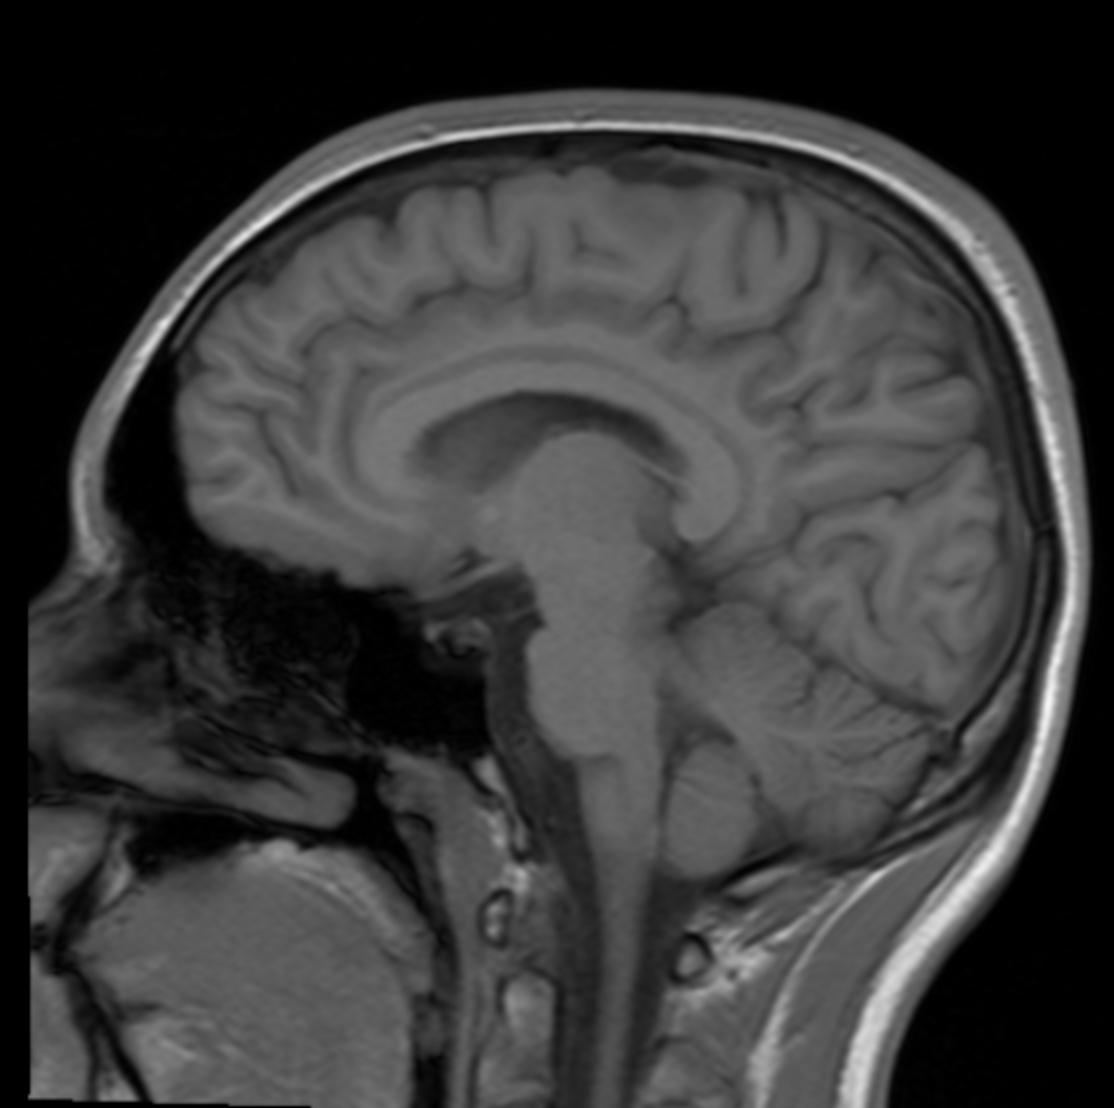

Your brain

File: Screenshot 2026-03-25 at 20.09.12.png 📥︎ (621.94 KB, 1114x1108) ImgOps

>>15717242

didnt get the nameroll, but here you go anyway